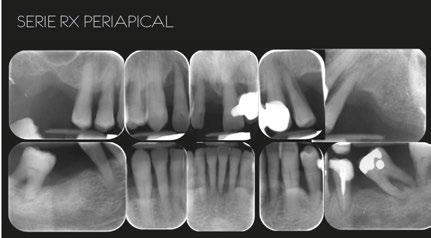

–Implante inmediato en incisivo lateral superior con técnica de «Socket Shield» y acceso vestibular para legrado de la lesión periapical, por el Dr. Ignacio Tormo Jiménez y cols. [106]